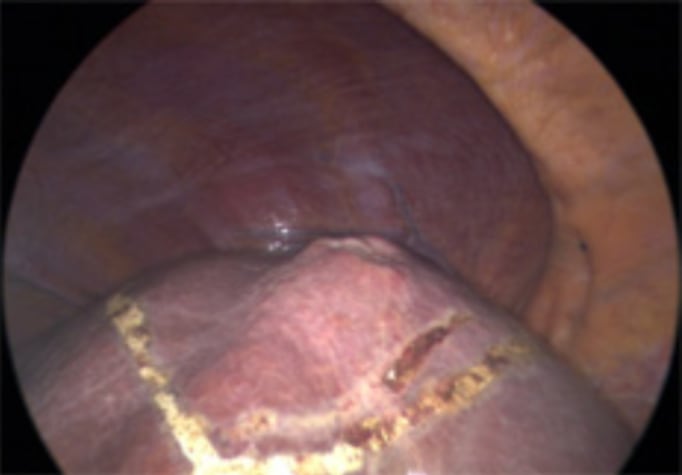

Placement of stay suture

Nonanatomical resection using CUSA